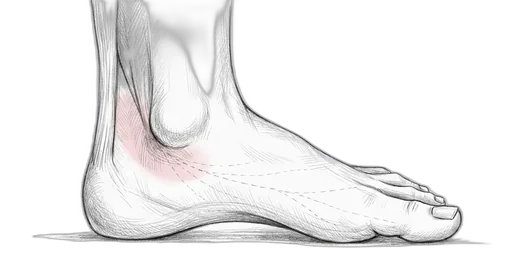

Foot & Ankle Exercise Guide

Choose your condition below to get started with exercises and stretches designed by Dr. Patish.

Pick your condition below, and you'll find your personalized exercise program — with medical illustrations, step-by-step instructions at three intensity levels, and clear guidance on when to call our office. Every protocol here is the same one Dr. Patish prescribes to patients in the clinic.

Heel & Arch

Achilles & Calf